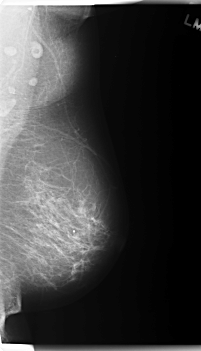

C_0179_1.LEFT_MLO

C_0179_1.LEFT_CC

LEFT_MLO LINES 5960 PIXELS_PER_LINE 3416 BITS_PER_PIXEL 12 RESOLUTION 50 NON_OVERLAY

LEFT_CC LINES 6000 PIXELS_PER_LINE 3256 BITS_PER_PIXEL 12 RESOLUTION 50 NON_OVERLAY